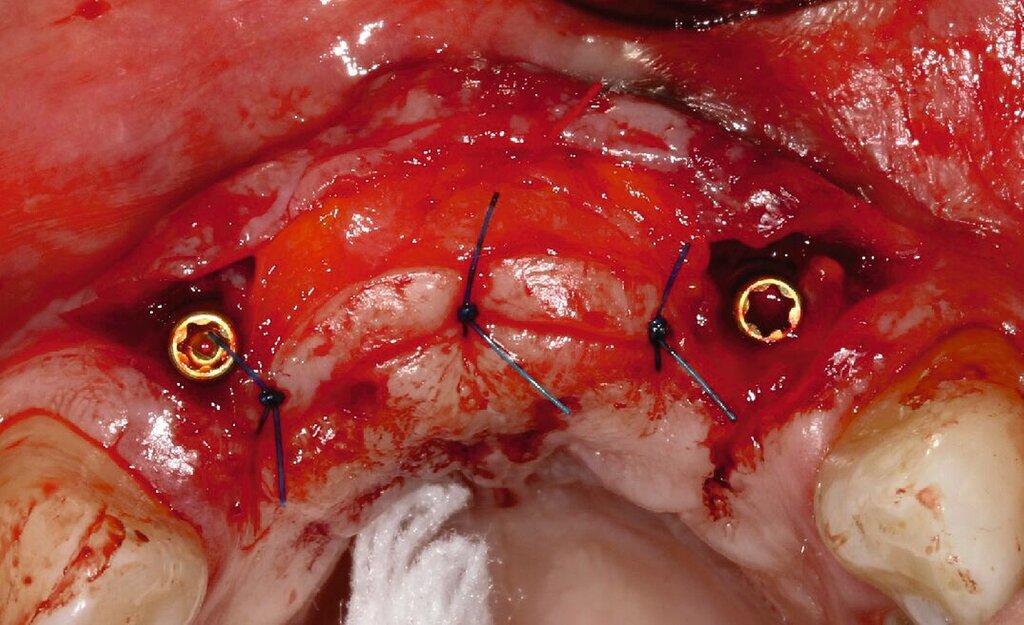

Da sechs Monate nach der Explantation keine nennenswerte knöcherne Regeneration festzustellen war, wurde eine zweizeitige Implantation nach Knochenaugmentation mithilfe dünner Knochenscheiben aus dem Kieferwinkel geplant. Die Entnahme erfolgte mit oszillierenden Instrumenten (Piezosurgery). Der Knochenblock wurde in dünne Scheiben geschnitten und mit Osteosyntheseschrauben am Alveolarfortsatz fixiert (Abb. 3e). Darüber wurden die Weichgewebe dicht vernäht. Weitere fünf Monate später erfolgte die Schraubenentfernung und die Implantation von zwei Bone-Level-Implantaten in regio 12 und 22 mit geschlossener Einheilung (Abb. 3f und 3g). Bei der Implantatfreilegung weitere sechs Monate später wurden die Weichgewebsdefizite im Brückengliedbereich durch ein kombiniertes Bindegewebs-/Schleimhauttransplantat aufgefüllt und gleichzeitig die keratinisierte periimplantäre Gingiva und Alveloarmukosa verbreitert (Abb. 3h und 3i). Die prothetische Versorgung erfolgte erst weitere drei Monate später, nach dem Konsolidieren der Weichgewebe. Die umfangreichen Augmentationsmaßnahmen konnten das transversale Weichgewebsdefizit vollständig kompensieren, während das verbleibende vertikale Defizit zu zervikal etwas längeren Kronen und Brückengliedern führte. Aufgrund der guten Abdeckung durch die Oberlippe kann das ästhetische Ergebnis als zufriedenstellend bewertet werden (Abb. 3j bis 3l).